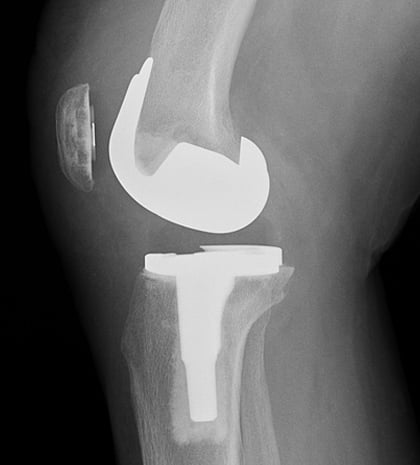

The selection of knee replacement prosthesis design and materials depends on each individual patient. The main implant components are made of metal – usually titanium or chrome-cobalt alloys. The implants are fixated in place either with a cement bonding agent or by osseointegration, in which the patient’s bone grows into a porous metal surface. A plastic platform or spacer will be inserted between the tibial and femoral implant surfaces. The spacer is made of polyethylene.

Most femoral components are made of metal alloys (cobalt chromium) or metal-ceramic alloys (oxidized zirconium). The patellar component is plastic (polyethylene). The tibial insert component is also plastic (polyethylene). The tibial tray component can be made of the following materials:

Lateral (side-view) X-ray of total knee replacement implants.